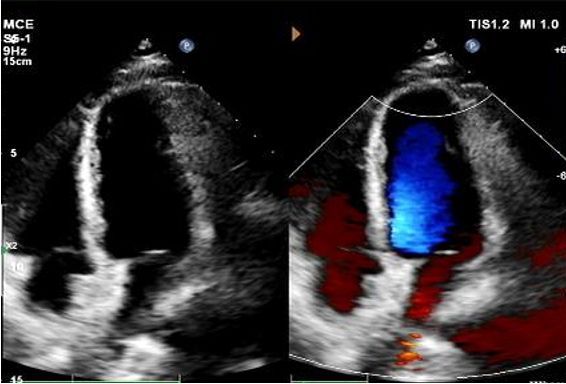

Today, we share a remarkable case highlighting 1-year post-op outcomes of MemoSorb in treating a complex long-tunnel PFO (12mm length, 1.4mm width), with a focus on serial echocardiographic evidence of device degradation and clinical symptom resolution.

Implante: 2424 MemoSorb®Oclusor PFO biodegradável implantado sob orientação eco e DSA.

Principais resultados de imagem de acompanhamento

Dias 1 a 9 meses:

Nenhum desvio residual observado.

Redução gradual da ecogenicidade do dispositivo.

Eco de 1 ano:

No visible disc structures – replaced by 8mm tissue thickening at the septal implant site.

Zero residual shunt (rest or post-Valsalva).

Absorção completa do dispositivo confirmada.